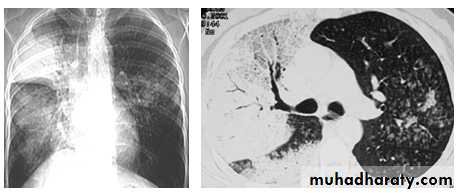

BRONCHOPNEUMONIA

Mycoplasma pneumonia. A 35 year old man presents with nonproductive cough and fever